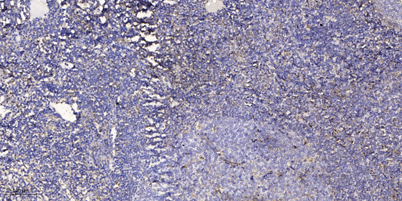

IF

IHC

Recomended Dilution Immunohistochemistry: 1/100 - 1/300. ELISA: 1/10000. Not yet tested in other applications.